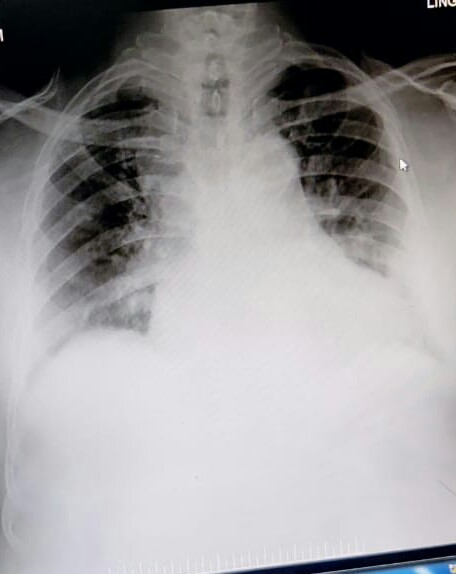

A 73 YEAR OLD MALE PATIENT WITH PEDAL EDEMA, SHORTNESS OF BREATH AND DECREASED URINE OUTPUT

A 73 yr male patient teacher by occupation, resident of .............. presented to Opd with chief complaints of :

- PEDAL EDEMA ,SINCE 15 DAYS

- SHORTNESS OF BREATH, SINCE 4 DAYS

- DECREASED URINE OUTPUT ,SINCE 2 DAYS

SOB since 4 days which progressed from grade 2 to grade 3 associated with orthopnea and PNS, unable to sleep due to sob since 4 days.

decreased urine output since 2days.